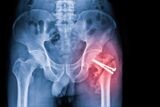

Почему переломы бедра у пожилых опаснее, чем кажется на первый взгляд

Фотография: Peterburg2.ru

С возрастом даже незначительная травма может обернуться серьезными последствиями. Особенно это касается переломов бедра у пожилых людей. На первый взгляд кажется, что речь идет о стандартной травме, но на деле ситуация куда сложнее. По оценке Петербург2.ру, число подобных случаев в мире неуклонно растет, и к 2050 году может превысить 4 миллиона ежегодно.

Причины переломов бедра у пожилых разнообразны. Наиболее частый фактор - остеопороз, который особенно часто встречается у женщин старшего возраста. Слабость мышц, проблемы с равновесием, хронические заболевания вроде диабета или анемии, а также снижение массы тела - все это увеличивает риск. Иногда перелом происходит даже без падения: достаточно неудачно встать с кровати или сделать шаг. В таких случаях речь идет о патологических переломах, когда кость уже ослаблена болезнью.